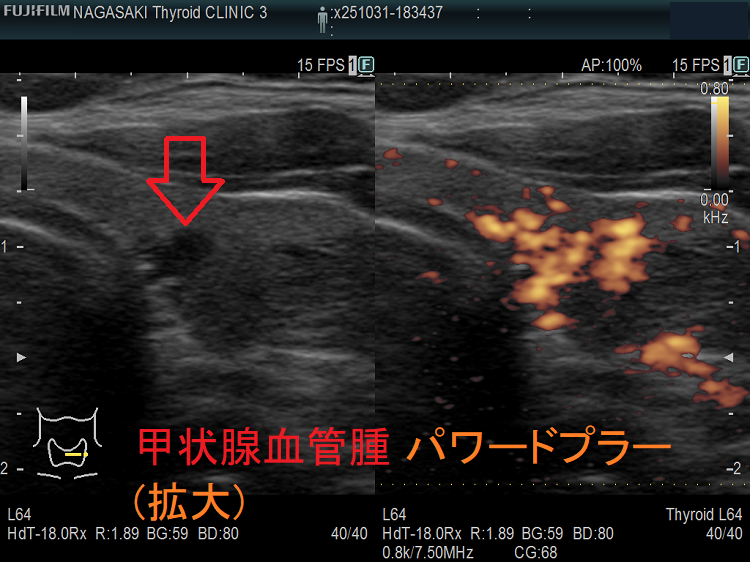

甲状腺に発生する血管腫は非常に稀で、日本の報告例もわずかです(日臨外会誌 72(3),579―583,2011)。

ケース①

ケース②

ケース③

甲状腺血管腫(拡大) ドプラーモード(eFlow);腫瘍内血管が3次元的に見え、毛玉の様。

ケース④